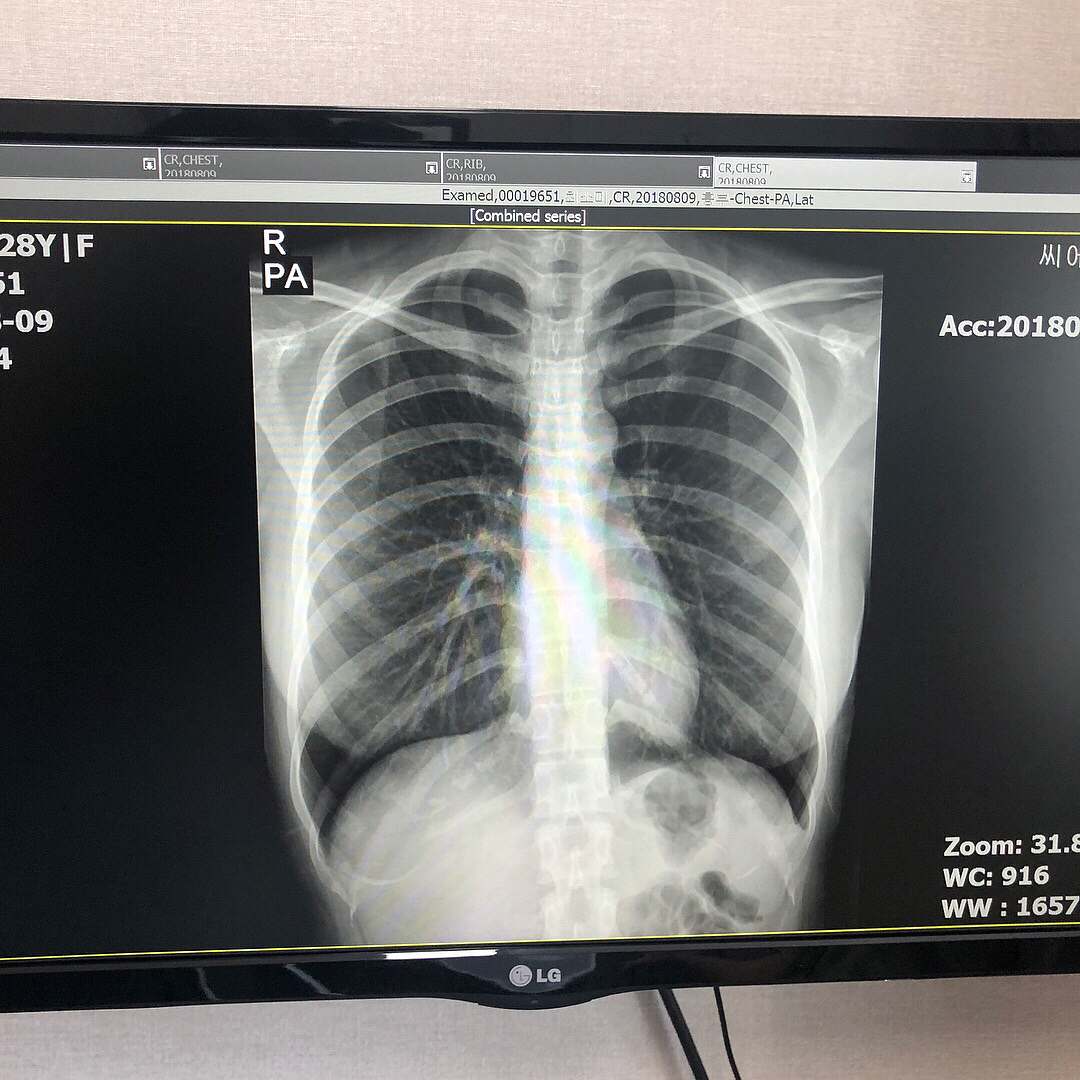

南韓網絡女主播崔素美(최소미Choi Somi)以甜美長相與魔鬼身材,擄獲不少粉絲心,讓她迅速走紅,在IG帳號上擁有70萬粉絲。但因她前凸後翹、激凸上圍等過於完美的身材,加上身處韓國一直飽受「整形傳聞」。為了反擊傳聞,日前崔素美公布醫師的鑑定資料,包括診斷書,還有一張胸部的X光照,可以看出裡面真的沒有任何人工植入物。

因五官神似郭雪芙的南韓網紅「崔素美」擁有白皙肌膚、性感S曲線身材,也常不吝在IG展現自己的好身材,不論是泳裝、深V禮服照,都讓粉絲鼻血直流,日前崔素美疑似受不了流言蜚語,索性直接去醫院照X光,並po文表示證明胸部裡沒填充物,一切都是「真材實料」。

「崔素美」發文表示,常看到有人好奇她是否去隆乳,直指她絕對是動過刀才有現在的好身材,為阻止這個謠言繼續擴散,她決定讓證據說話,並曬出她胸部的X光照,上頭寫到胸部內並無填充物,她希望透過這次能夠平息沒有根據的傳聞。不少粉絲看完紛紛打氣,希望她不要在意酸民留言,但也有網友認為,還是要實際「雙掌鑑定」才能斷定真假。